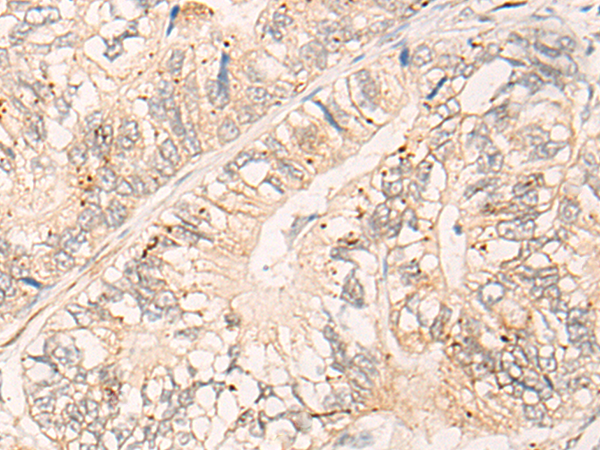

IHC positive control: |

Human liver cancer and Human gastric cancer |

IHC Recommend dilution: |

25-100 |